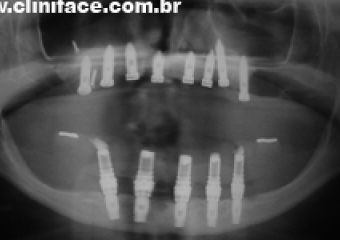

Raio X após instalação dos implantes - Clínica Cliniface

Raio X após instalação dos implantes